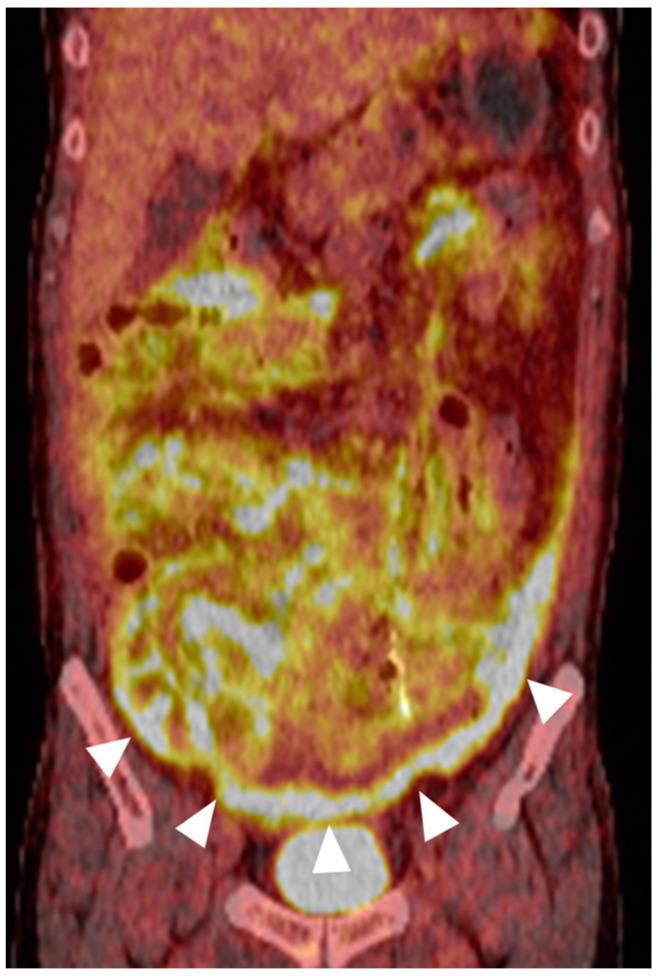

Myeloid sarcoma, a rare extramedullary manifestation of acute myeloid leukemia (AML), can occur in various anatomic sites but seldom involves the gastrointestinal tract. We report the unusual case of a 49-year-old man with a history of AML who initially presented with abdominal pain and imaging findings suggestive of a paracolic abscess. However, the lesion rapidly progressed to a large descending colon mass with peritoneal involvement over five weeks. Surgical resection and histopathological examination confirmed a diagnosis of myeloid sarcoma. This case highlights the potential of myeloid sarcoma to mimic an inflammatory colonic process at initial presentation prior to manifesting as an overt mass lesion. Although exceedingly rare, myeloid sarcoma should be considered in patients with a history of AML presenting with colon lesions, particularly in those with an aggressive clinical course. Early recognition may expedite appropriate treatment and prevent unnecessary procedures. This report also underscores the importance of correlating imaging findings with clinical history and histopathology findings to establish an accurate diagnosis.

髓系肉瘤是急性髓系白血病(AML)一种罕见的髓外表现,可发生于各种解剖部位,但很少累及胃肠道。我们报告了一例不寻常的病例,一名49岁有AML病史的男性,最初表现为腹痛,影像学检查结果提示结肠旁脓肿。然而,在五周内,病变迅速进展为降结肠巨大肿块并累及腹膜。手术切除及组织病理学检查确诊为髓系肉瘤。该病例突出了髓系肉瘤在最初表现为明显肿块病变之前,可能在初始表现时模拟炎性结肠病变的可能性。尽管极为罕见,但对于有AML病史且出现结肠病变的患者,尤其是那些临床病程进展迅速的患者,应考虑髓系肉瘤。早期识别可能会加快适当治疗并避免不必要的手术。本报告还强调了将影像学检查结果与临床病史及组织病理学检查结果相关联以建立准确诊断的重要性。